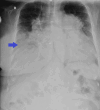

The diagnosis of atrial septal defect (ASD) may be delayed until adulthood or even later in life as it is a well-tolerated congenital heart disease. If patients are not examined and investigated well in childhood, the diagnosis may be delayed until later in adulthood when patients present with palpitations and sometimes dyspnea due to the right chambers dilatation from right ventricular volume overload. In this report, we present a case of a 50-year-old female patient with symptoms of heart failure and atrial fibrillation who was found to have dilated right cardiac chambers, dilated pulmonary artery, severe tricuspid regurgitation, pulmonary hypertension, and a pulmonary-to-systemic flow ratio (Qp/Qs) of more than 1.5 by transthoracic echocardiography and Doppler, indicating left to right shunt at the atrial level. However, transthoracic echocardiography could not visualize the defect, and two-dimensional (2D) transesophageal echocardiography was done in this patient and documented the presence of a sinus venosus ASD with an incomplete cor triatriatum dexter membrane; all four pulmonary veins were identified going to the left atrium. Since the presence of an incomplete cor triatriatum dexter membrane (despite causing no symptoms) makes the percutaneous closure of the sinus venosus ASD and the percutaneous repair of tricuspid regurgitation very difficult, we decided to advise surgical ASD closure and tricuspid valve repair for the patient.